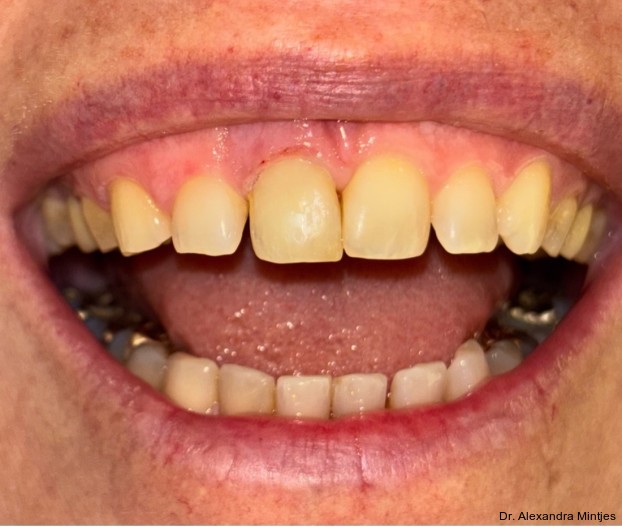

Bei der Erstvorstellung zeigte die vorhandene Füllung einen deutlichen Randspalt, war verfärbt und nach apikal hin insuffizient. Klinisch präsentierte sich ein dicker gingivaler Phänotyp mit ­harmonischer Weichgewebsbalance, jedoch bestand distal eine lokalisierte, entzündliche Zahnfleischtasche (Abb. 1). Es war zu vermuten, dass das nekrotische bzw. resorptive Hartgewebe nicht vollständig entfernt worden war. Auf dem DVT wurde das Ausmaß des Defekts deutlich. Zu­dem ließ sich eine deutliche apikale Aufhel­lung nachweisen, die Patientin war jedoch beschwerdefrei (Abb. 2).

Die Diagnose lautete eine invasive zervikale Resorption Klasse 3 nach Heithersay. Dieses Sta­-dium beschreibt eine tiefe Resorption mit Ausdehnung in das koronale Dentin und das zervikale Drittel der Wurzel, ohne dass die Pulpa vollstän­dig involviert ist. Solche Läsionen gelten als prognostisch kritisch und führen in der Regel zu einer extraktiven Therapie.